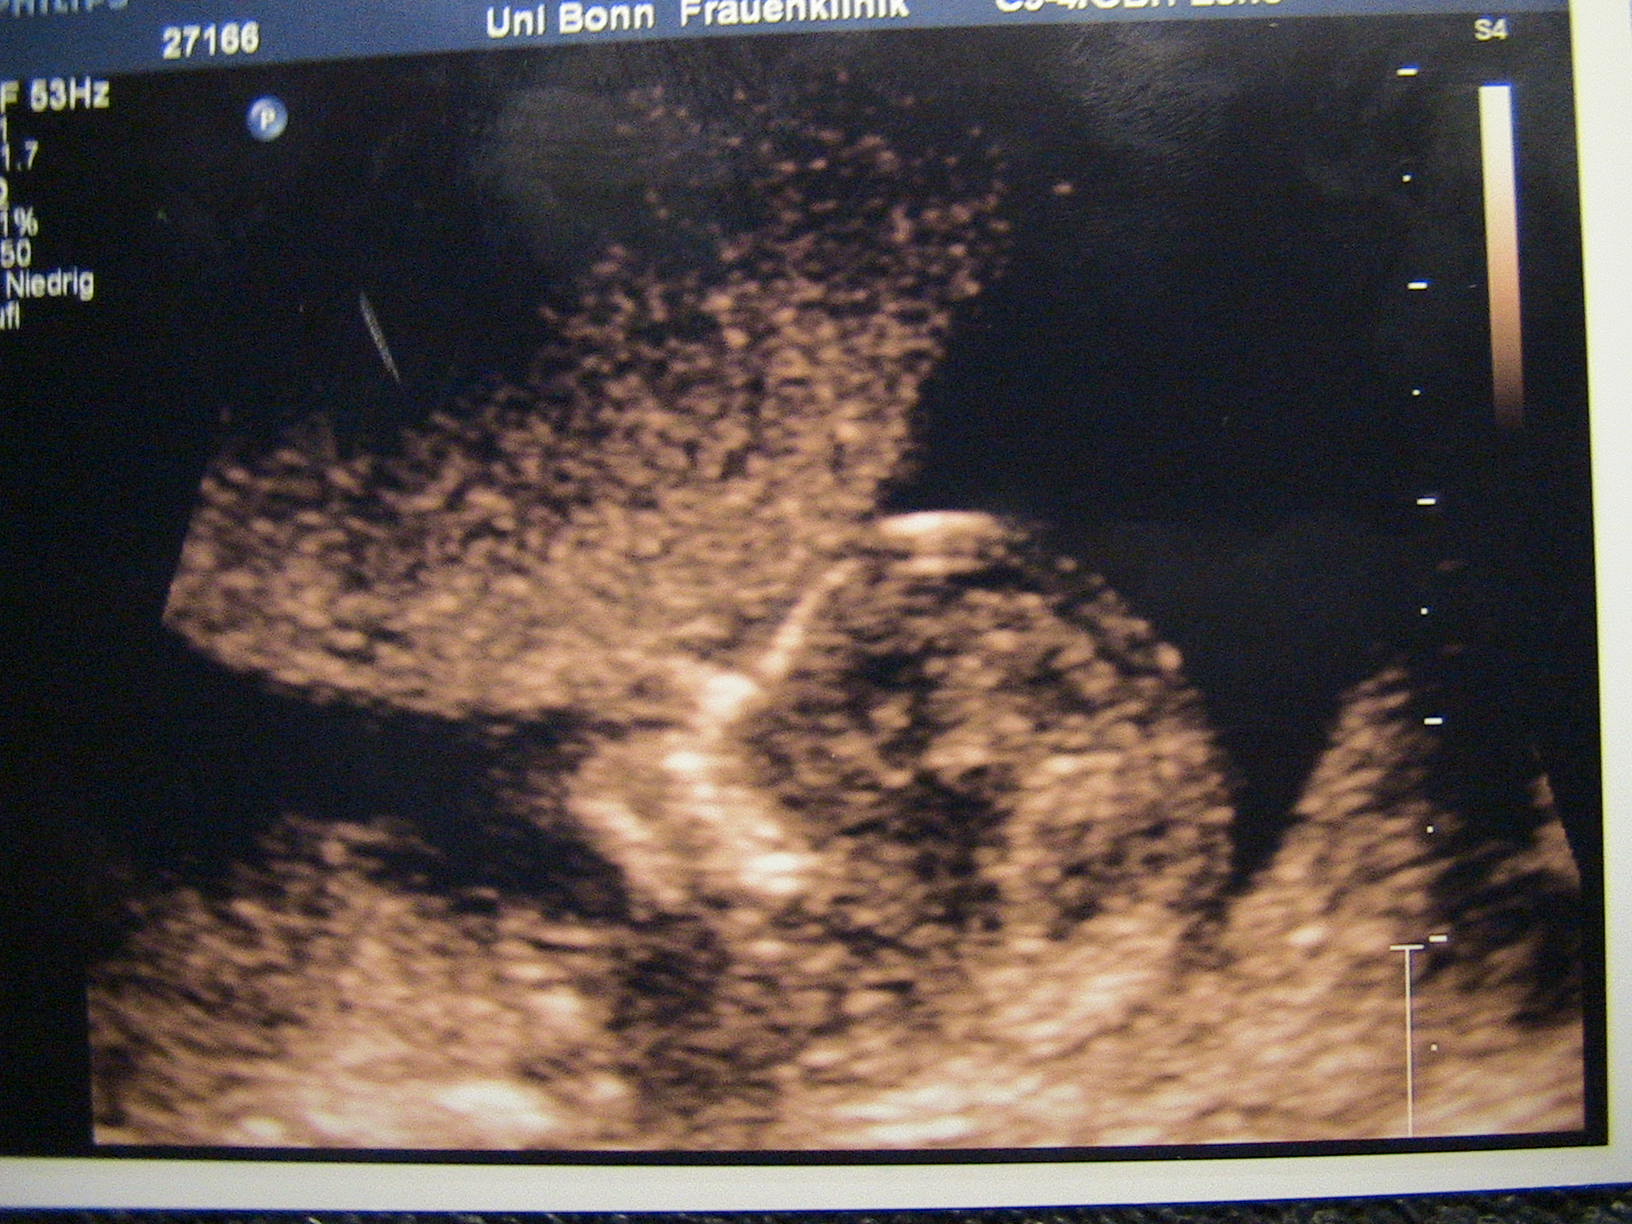

Jaqueline: Ich freu mich wirklich wahnsinnig für euch!!! Gratulation zur NFM und zum Jungen und überhaupt!!!!

Jaqueline: Gratulation zum Sohn

@Jaqueline: Wie süüüüüüüüüüüss!! So ein kleines Würmchen!!!

@Jaqueline: Herzlichen Glückwunsch zum Sohnemann!!!!! Jetzt schon lässig euer Kleiner, im Schneidersitz mit den Füssen winkend!!!